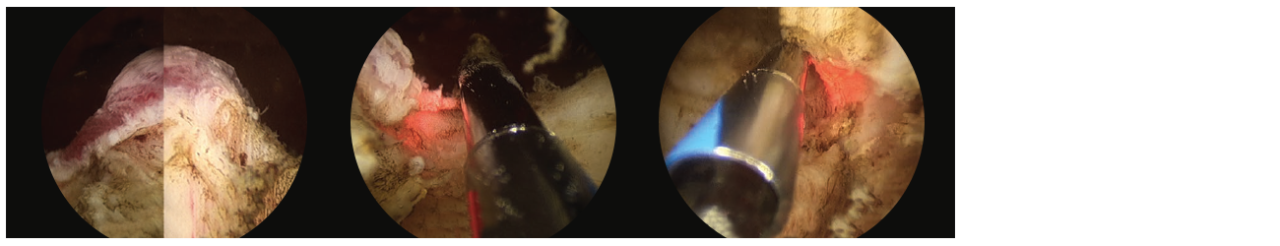

• Then comes the heart of the procedure, in which I systematically debulk the prostate by using the laser to remove the adenoma (non-malignant prostate tissue) off the surgical capsule, pushing tissue pieces that are too large to be vaporized into the bladder. (Fig. 3)

3 scope images. Identifying verumontanum. Figure 3, Part 1: VIT along capsule of floor tissue.

Additional 3 scope images. Identifying verumontanum. Figure 3, Part 2: VIT along capsule of floor tissue.